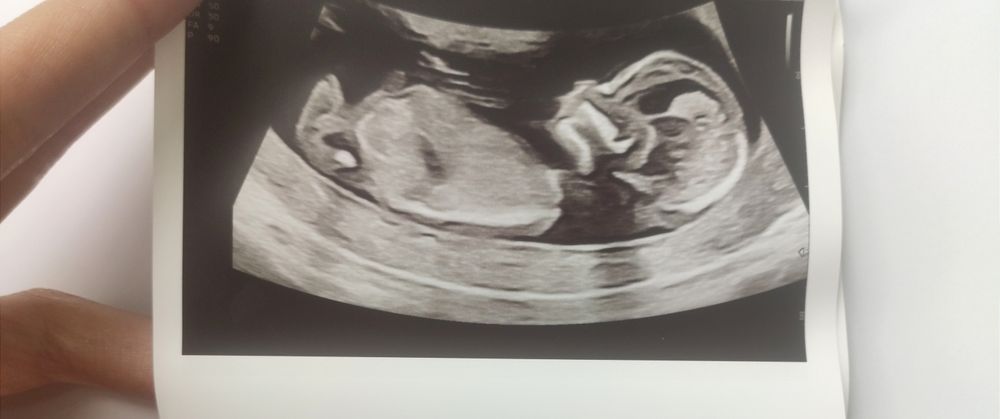

Первый скрининг

Девочки , кто умеет определять пол ребенка ? Подскажите пожалуйста мальчик или девочка ?